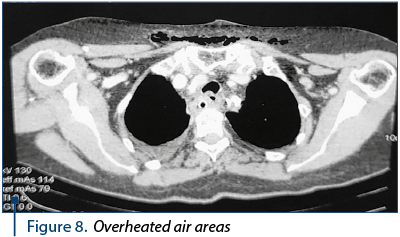

The CT scan 2944 performed on March 16, 2016, at five days postoperatively, consisted of the diffuse infiltration of the retrolaryngeal mass with a mass effect at the laryngeal level and the left anterolateral dislocated esophagus with diffuse parietal thickening; cervical posterior air areas with mediastinal-cervical drainage (Figure 8); posterior mediastinal infiltration zone in the upper and middle third adjacent to the esophagus. Bilateral pleural fluid. Gastrostomy present; subcutaneous emphysema of the cervical and thoracic region.

Figure 8. Overheated air areas